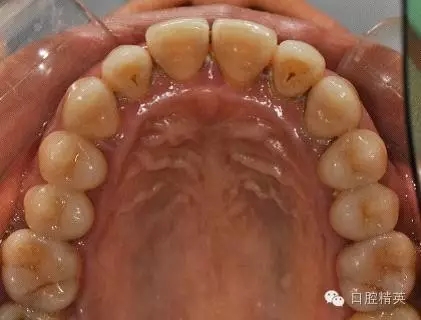

本病例 :女 34歲,主訴刷牙出血,覺牙齒輕度松動一年。

檢查見大量齦上及齦下結(jié)石,探診出血,牙周袋較深,32-42 II度松動。X線片顯示牙槽骨水平吸收。

治療前: